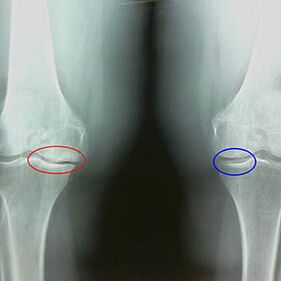

Features x -early arrival of the second phase of knee illegal:

- The pointed edges of the Inter -Scrip tubercles on the tibia, where the cross -shaped ligament is attached;

- narrowing of the joint gap on the medial side;

- The pointed edges of bones condyli on the medial sides, less often in lateral, depending on the development of the Valgus or Varor joint deformation.

For the second phase of LarsenThe narrowing of the joint gap of over 50% is characteristic, but this can only be controlled in dynamics or comparison with a different joint.

The X -ray shows the presence of osteophytes, a change in the space between the femoral bones and tibia, which indicates the loss of cartilage in the knee.Sometimes radius X of the knee joints shows significant signs of cartilage wear, but patients do not feel significant pain.On the contrary, the arthrosis of the first stadium can stop the function of the knee, since the cause of pain are the hypotonic muscles.